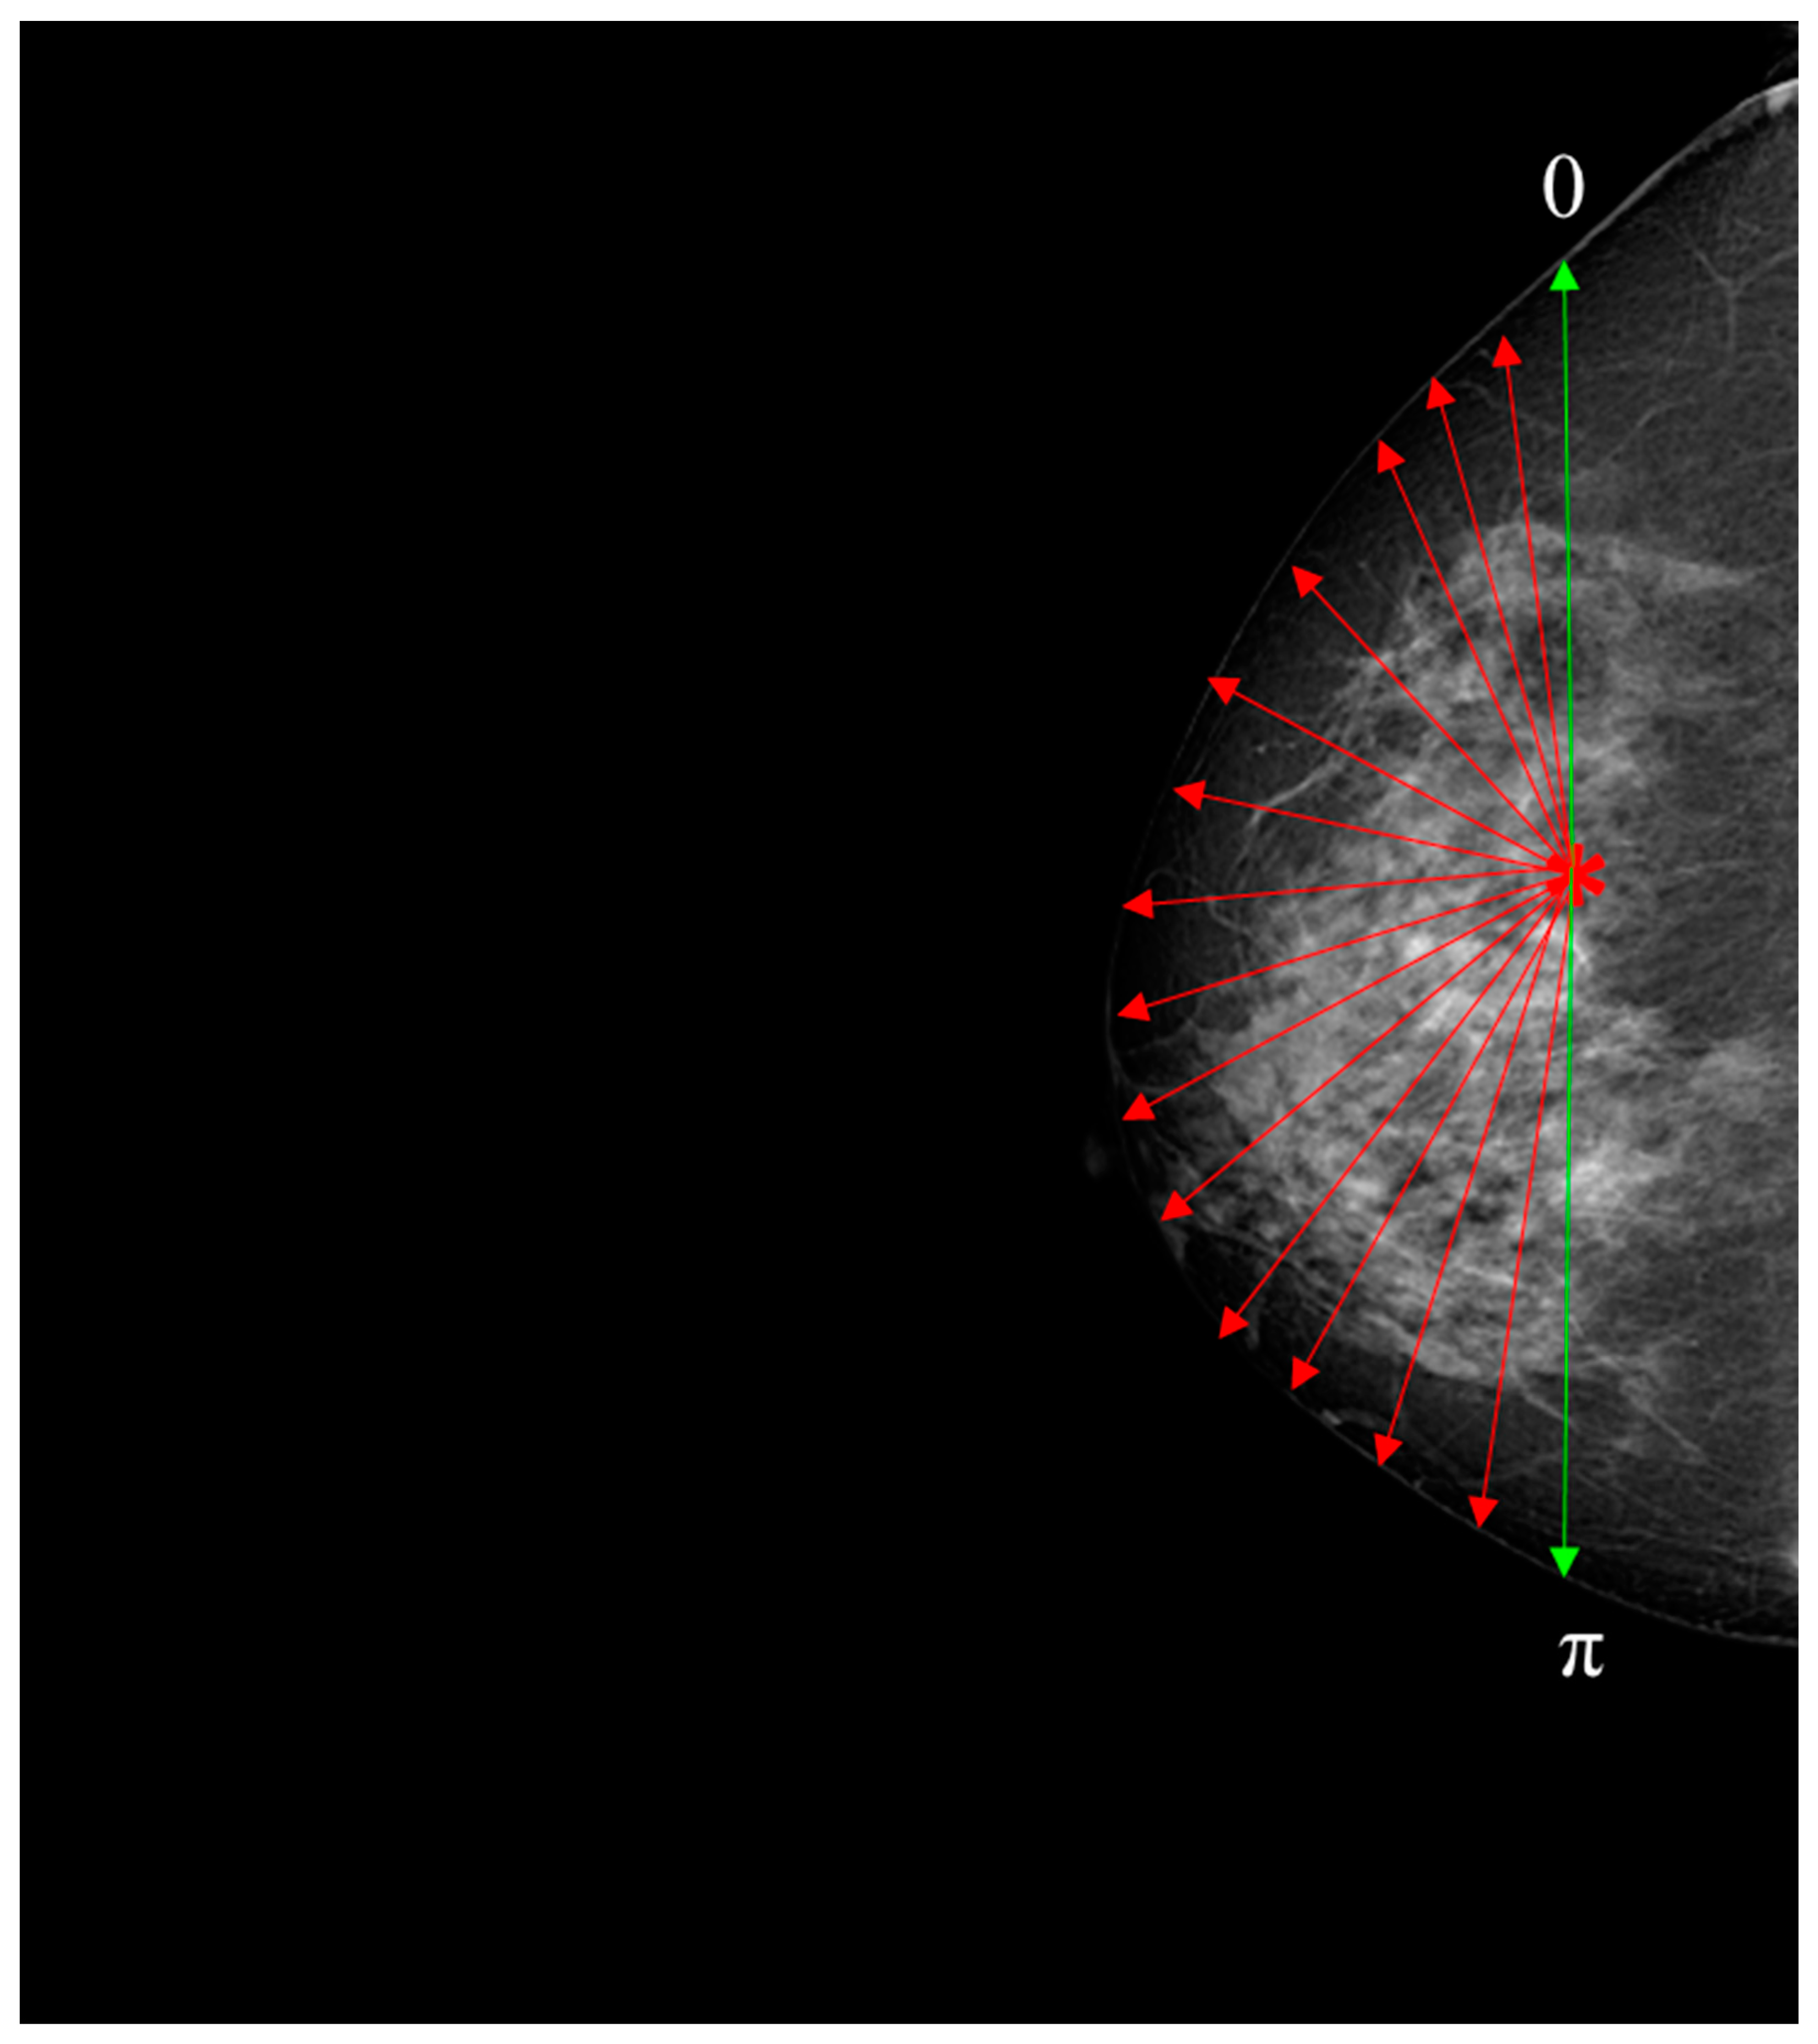

An approach to analyzing breast asymmetry is to compute a collection of radii formed between the centroid and the skin perimeter. Once the centroid is computed, the radius is retrieved based on the angle as the argument between [0, π] radians in steps of one radian, creating a distance for each orientation between the centroid and perimeter of the skin. This supports uniformity and ensures that the image is created using the outermost breast pixels. To handle variations in breast size and shape among different DICOM images, the distances between the centroid and the skin perimeter were normalized to fall within the range of [0, π]. This normalization process ensured that the spatial features used for evaluation were consistent and comparable across all images, regardless of their individual radii. By generalizing this approach to the entire dataset, we were able to effectively evaluate the morphological asymmetry in breast skin thickness and its potential significance for early breast cancer detection.

Nevertheless, an important factor to consider is the orientation of the breast. Hence, both images (i.e., left, and right breast images) were adjusted to the same orientation, i.e., towards the right. The hypothesis proposes that the set of distances would differ between left and right views of the breast. To maintain consistency and ensure direct comparability, all images were oriented toward the right. Although orienting the image set towards the left is feasible, it would necessitate image reprocessing and algorithm adjustments to adjust the left-oriented images. Our specific focus on the right-oriented images allowed us to investigate the impact of asymmetry on the right breast and evaluate the effectiveness of our proposed approach. Figure 3 presents the flowchart used to obtain a collection of distances between the centroid and the edge of the breast, depicted in Figure 4. Appendix A provides the pseudocode for the algorithm.

Figure 4. This diagram serves as an illustrative representation demonstrating the process of deriving a set of distances between the centroid and the periphery of the breast. The centroid is indicated by the asterisk symbol, while the red radius is depicted as arrows extending towards the edge of the breast and the green arrows indicate the beginning and ending [0–π].